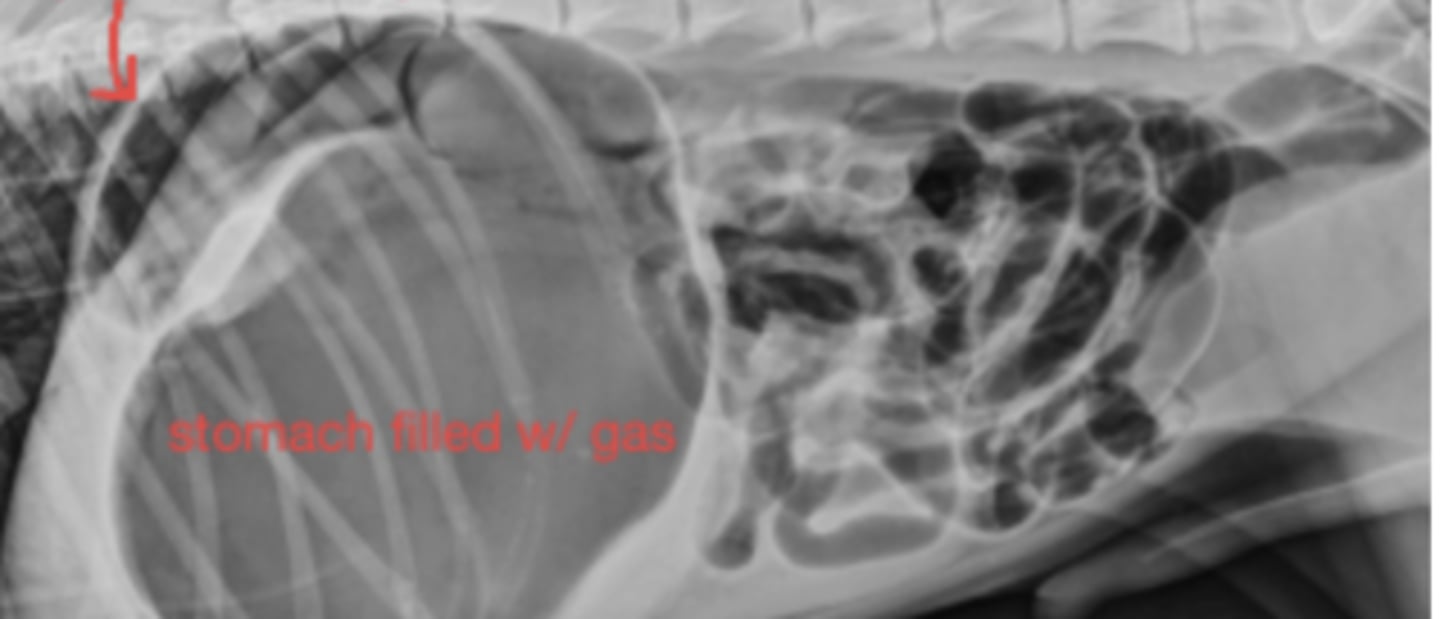

Linear foreign body

Dx of cat vomiting;